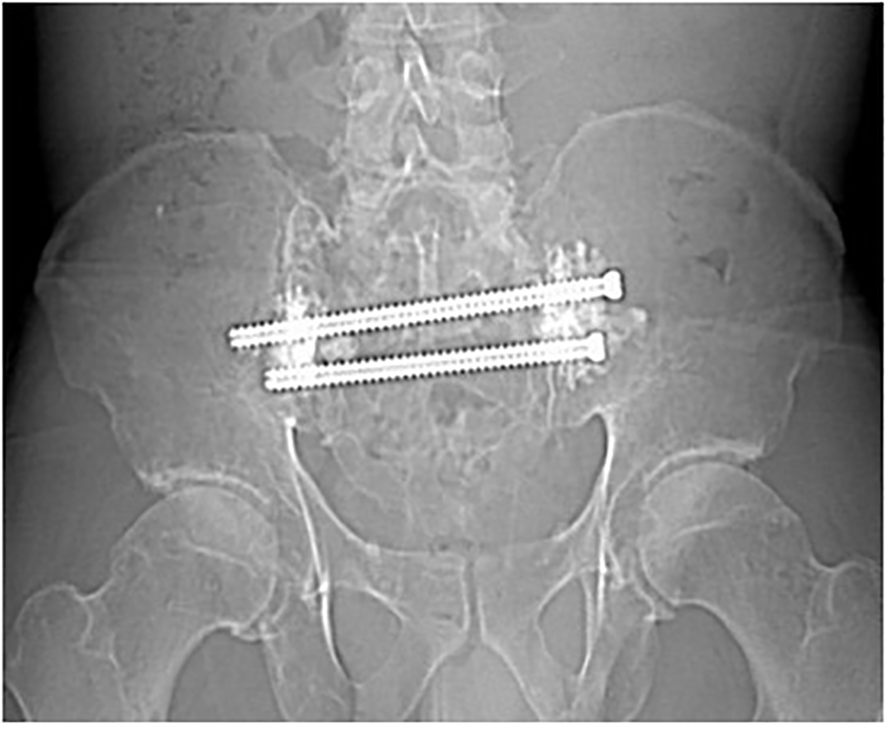

Figure 5

Radiograph made 9 months following CT-Fluoroscopic guided trans-sacral screw fixation with sacroplasty, showing stability with no evidence of screw loosening.

Incisions were closed with 3-0 Monocryl sutures and Dermabond. Following the procedure, a 1-week follow-up visit was standard, with additional visits being requested at 1 month and 3 months thereafter, while also attempting to schedule visits that coincide with other medical oncology visits the patient may have. Radiographs were obtained during follow up visits (Figure 5).